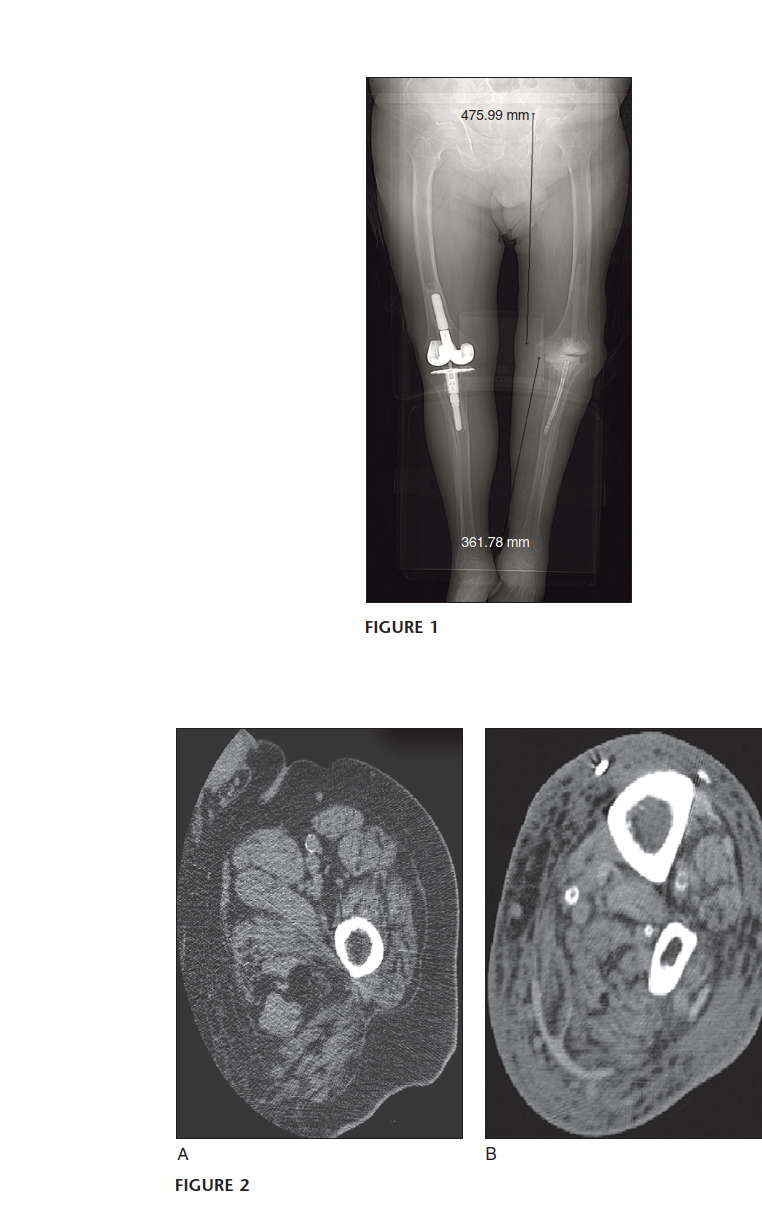

* Plain Radiographs: Anteroposterior (AP) and lateral plain films of the affected knee are mandatory. Crucially, full-length standing AP and lateral radiographs of the entire lower extremity from hip to ankle are indispensable.

* These films allow for accurate assessment of overall limb alignment, identification of any pre-existing bowing or deformity in the femur or tibia, and determination of the appropriate fusion angle.

* Radiographic magnification markers should be used to enable accurate templating of nail length and diameter.

* They provide information on bone stock, potential bone defects, and any remaining hardware.

* The length of the femur and the tibia must be determined, and any unusual bowing or canal abnormalities must be identified. The length of the femur and the tibia can be obtained from plain radiographs with a measuring template in place.

* Computed Tomography (CT) Scan:

* A computed tomography (CT) scan from the tip of the trochanter to the distal femur and then from the proximal tibia to the distal tibia can be used. This provides detailed information regarding the intramedullary canal dimensions, particularly identifying the narrowest portion or isthmus of the tibia and femur, which limits the maximum size of the intramedullary nail.

* CT scans are invaluable for identifying any retained cement, previous screw holes that could interfere with new locking screws, areas of osteolysis, or complex bone defects.

* 3D reconstructions can be particularly helpful for visualizing complex deformities and planning reaming trajectories.